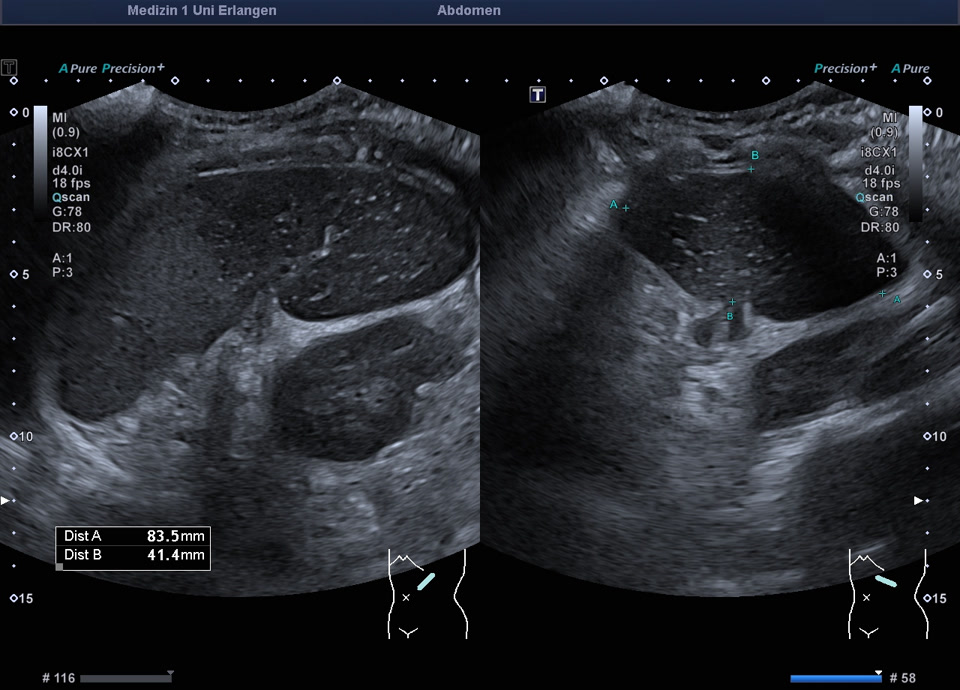

Splenic infarction

• Recent splenic infarction